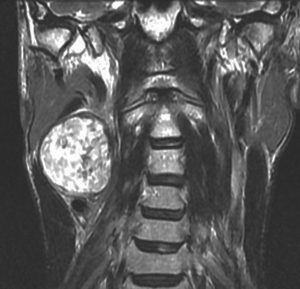

40歳の時に右頸部が腫れているのに気づいて発見され,耳鼻科で生検術され経過をみたものです。7年間の経過観察でかなり増大しました。症状は全くありませんでした。まだ腫瘍増大が止まらないので摘出することにしました。術前は舌咽神経鞘腫と診断することはできません。

手術中に中枢端で舌咽神経本幹に連続性がありここを切断して全摘出しました。それで舌咽神経鞘腫と確定診断ができています。

術後には無症状,他覚的な神経脱落症状はありませんでした。長い間かかって増大したので迷走神経などで代償機能が働いているのだと推定されます。

舌咽神経の末梢枝は,carotid sinusからの感覚神経を含むので,内頸動脈と外頸動脈の間に入り込むように増大することがあります。